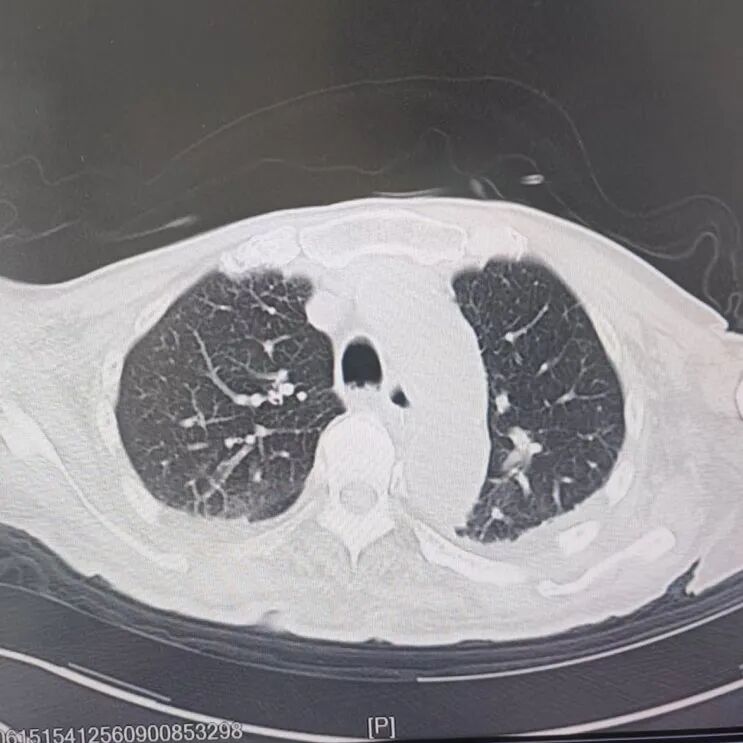

引言 / / Introduction 年近8旬的陈阿姨(化名)因脑梗长期瘫痪在床,康复期间突然高烧不退,体温升至39℃,在抗感染过程中,她并发高渗性脱水,病情急剧恶化,被紧急送入ICU。此时,她已气管切开,依靠呼吸机维持呼吸,并伴有低蛋白血症、低钾高钠血症及房颤等多种危重情况,命悬一线! PART. 01 多重泛耐药菌叠加大量基础病 治疗陷入“死胡同” 呼吸与危重症医学科及ICU通力协作,稳住患者生命体征。治疗过程中,进一步的病原学检查结果令人心惊:陈阿姨的肺部遭遇多种“超级细菌”混合侵袭,包括铜绿假单胞菌、鲍曼不动杆菌、嗜麦芽窄食单胞菌、金黄色葡萄球菌、木糖氧化无色杆菌、粘质沙雷菌等高度耐药菌,堪称耐药菌“大本营”。这些细菌对常用抗生素几乎全部耐药,治疗难度高,死亡率高。 治疗前患者肺部影像 PART. 02 多学科强强联手 量身定制攻坚方案 面对无药可用的困境,呼吸科没有放弃!宋刚主任带领团队联合药学部、检验科、重症医学科成立多学科治疗组,根据患者身体情况实时调整用药,逐一攻破耐药菌。这场与“超级细菌”的拉锯战持续了30多个日夜。 在医护日夜坚守和家属全力配合下,陈阿姨的感染终于被遏制:高烧退了,肺部阴影消散了!就在即将宣告胜利时,又发现她存在泌尿感染问题,随即转入泌尿外科协同治疗。当宋主任回访时,看到陈阿姨精神焕发、体温平稳,所有参与救治的人都感慨万分!这场救治,正是呼吸与危重症医学科攻坚耐药菌硬实力的生动体现! 治疗后患者肺部影像 从“无药可用”到“绝处逢生”,此次成功救治,集中体现了呼吸与危重症医学科以耐药菌精准诊治为核心的学科特色与技术优势。面对一次次的严峻挑战,科室始终秉持“生命至上、知难而进”的信念,以多学科协作为平台,凭借个体化精准用药策略,为患者寻找生机,为更多陷入困境的患者和家庭带去了实实在在的希望。 PART. 03 人民医院 人民名医 宋刚 主任医师 ·葫芦岛市第二人民医院呼吸与危重症医学科主任 ·辽宁省生命科学学会东北呼吸与危重症医学(PCCM)分会辽宁省基层委员会副主任委员 ·辽宁省细胞生物学学会放射粒子治疗专业委员会理事 ·辽宁省抗击新冠肺炎疫情先进个人 ·葫芦岛市劳动鉴定委员会专家库成员 ·葫芦岛市医学会呼吸内科学分会第三届委员会副主任委员 专业特色:擅长呼吸系统疑难及急危重患者的救治,如急慢性支气管炎、支气管哮喘、慢性阻塞性肺疾病、肺炎、肺栓塞、肺癌、间质性肺疾病、睡眠呼吸暂停综合征等,尤其擅长有创无创机械通气、支气管镜下相关检查及治疗(TBNA、气道支架置入术、球囊扩张等)、全肺灌洗术等领先技术,发表国家级期刊多篇。